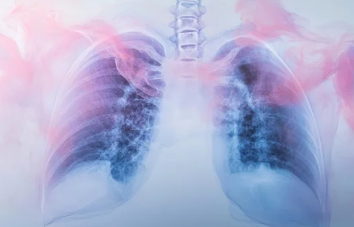

✅ 3) 흉부 CT (고해상도 CT, HRCT)

- 폐 섬유화 진행 여부 및 염증 상태를 정밀 분석

- 간질성 폐질환 진단의 핵심 검사